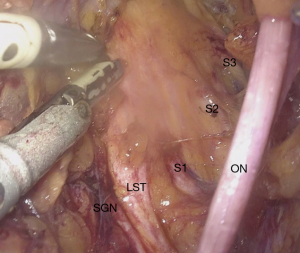

With the introduction of laparoscopic neuronavigation (LANN), first described by Possover et al., the visualization of retroperitoneal area with laparoscopy and the dissection of autonomic and somatic nerves under microscopic view became possible (110). Following this visualization of the lumbosacral plexus, nerve pathologies such as entrapment or direct involvement of the nerve fibers could be identified (94,111).

It has been shown with LANN that endometriosis is responsible for all the pathologies involving nerve fibers in the retroperitoneal area. According to Siquara De Sousa et al. in the presence of retroperitoneal endometriosis a 57% lumbosacral plexus involvement and a 39% sciatic nerve involvement has been reported (112). Possover et al. have shown that in the treatment of neural involvement of endometriosis, resection of endometrial tissue present within the nerve is possible without causing any neural complications (111). Endometriosis can also infiltrate into the sacral nerve roots. Sympathetic fibers are more affected than the somatic fibers, because the hypogastric fascia acts as a barrier against endometriosis infiltration (113). In 40% of patients with DIE and in 72% of patients with hypogastric endometriosis deep lateral pelvic endometriosis has also been observed (114). CPP was also reported as the main symptom and indicator of deep later pelvic endometriosis (114). Possover et al. reported that neurolysis of the sacral nerve roots is sufficient and unchallenging in the treatment of endometriosis involving sacral nerves since endometriosis does not infiltrate into the epineurium (111,113).

The second pathology which can be treated with the neuropelveological approach is the entrapment of a nerve. Entrapment can be caused by endometriosis, vascular malformations/dilatations, fibrosis and piriformis syndrome where the piriformis muscle fibers entrap the sciatic nerve (94). Previous surgeries, especially pelvic reconstructive surgery have been reported to be responsible for fibrosis in the retroperitoneal area (25,115). Laparoscopy should again be the first line treatment of neural entrapment especially in treating fibrosis following pelvic surgery (116).